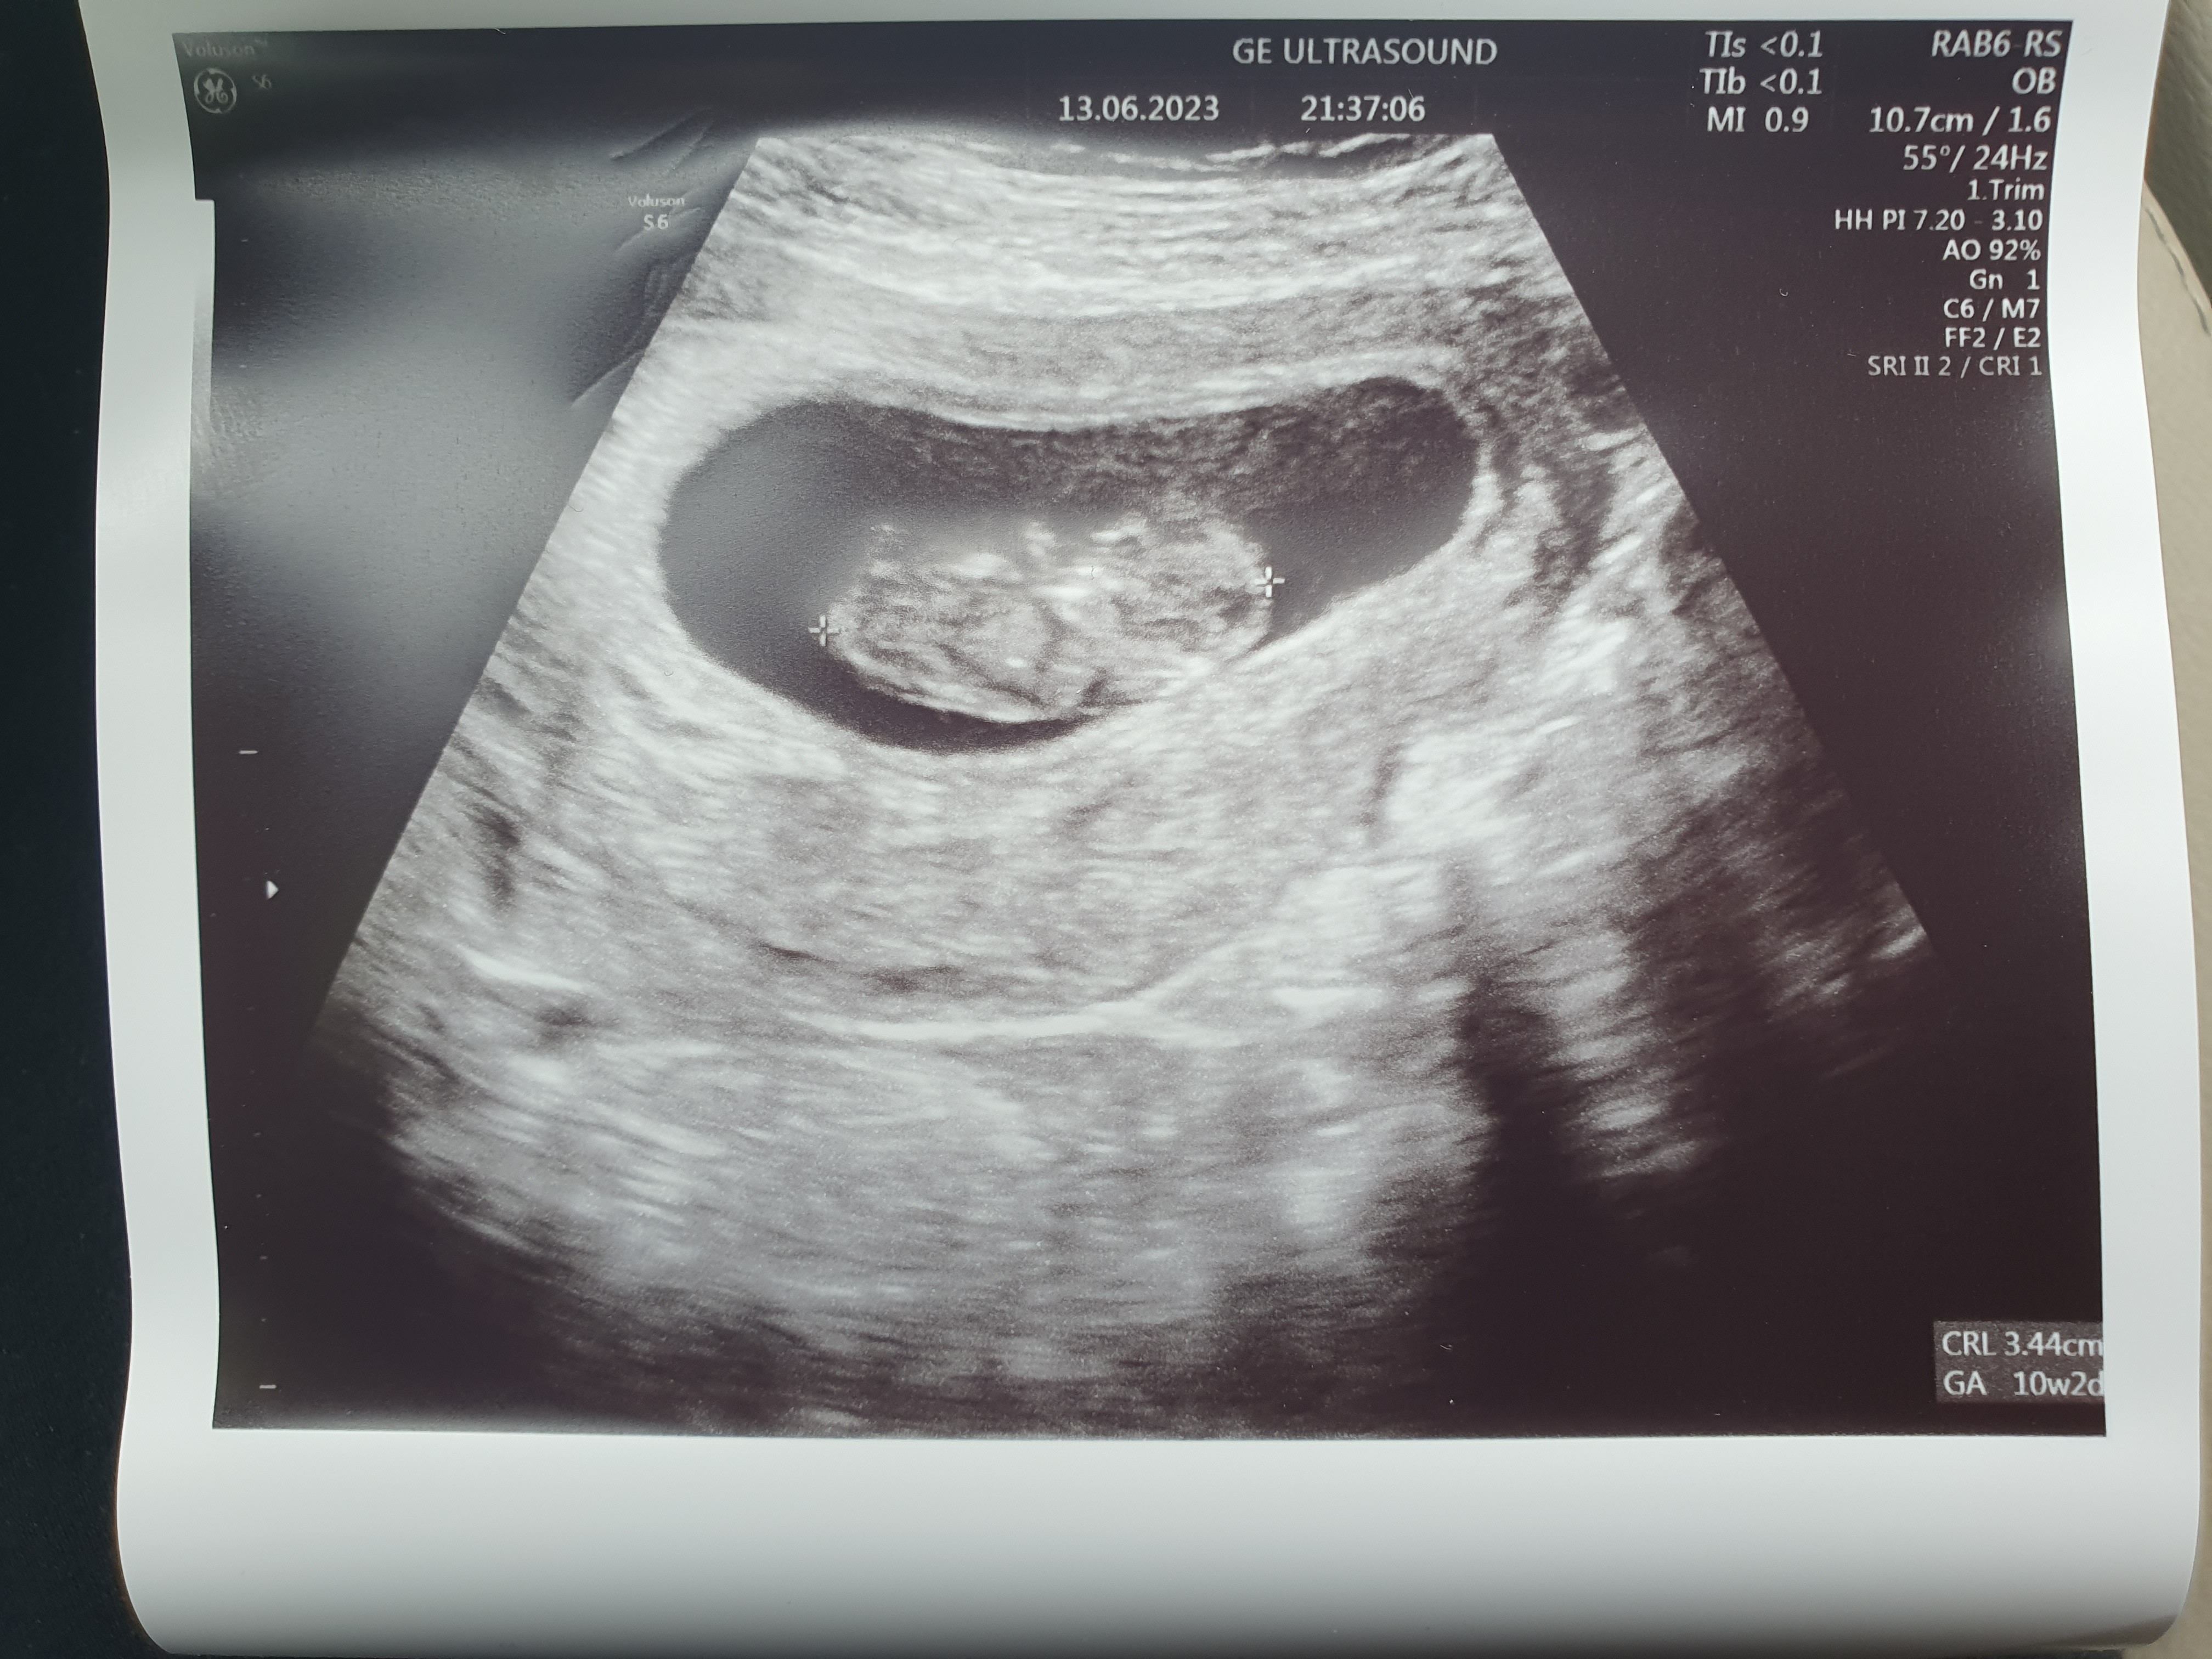

bez sensu, bo całą zimę nie chorowałam, a teraz, gdy wszystkie narządy się u dziecka rozwijały i nie można brać leków, to ja chora

Dziś wizyta o 14.45. Zbieram się, bo mam 100 km do dojechania,a dopiero wstałam, bo odsypiałam ostatnie dni